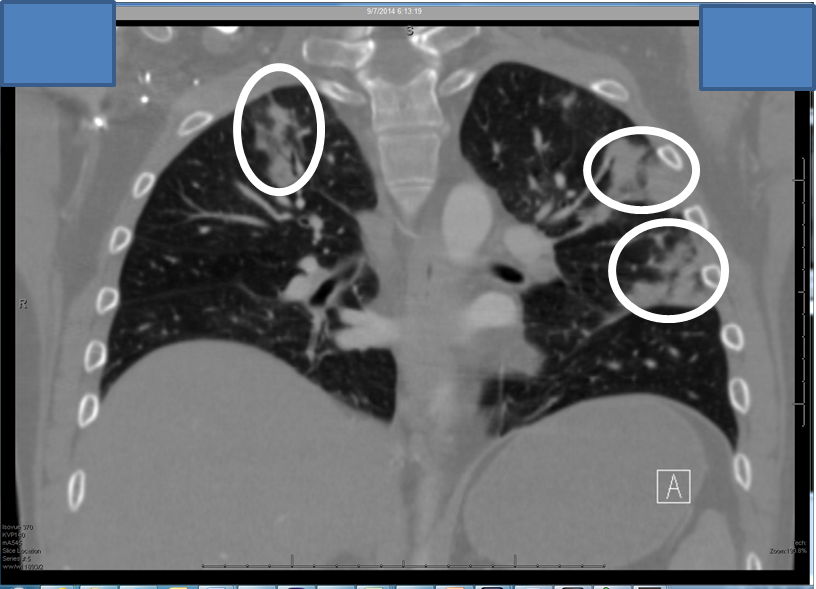

Fungal infection thesis picture This picture representes fungal infection thesis.